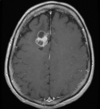

Linfoma SNC Tumor infiltrativo, supratentorial, atravessa a linha média Acomete a profundidade dos hemisférios cerebrais Realce intenso sólido, sem necrose Restrição a difusão Hiposinal T2

LINFOMA PRIMÁRIO DO SNC: 90% supratentoriais; Geralmente linfoma não hodgkin (celulas b); localização periventricular e nucleos da base; pode atravessar linha média (corpo caloso); TC: iso / hiperdensa com realce pos contraste; pode haver necrose; RM: Hipossinal em T1 e T2 com forte realce homogêneo pós contraste (realce anelar em imunossuprimidos); restrição a difusão;

Linfoma SNC